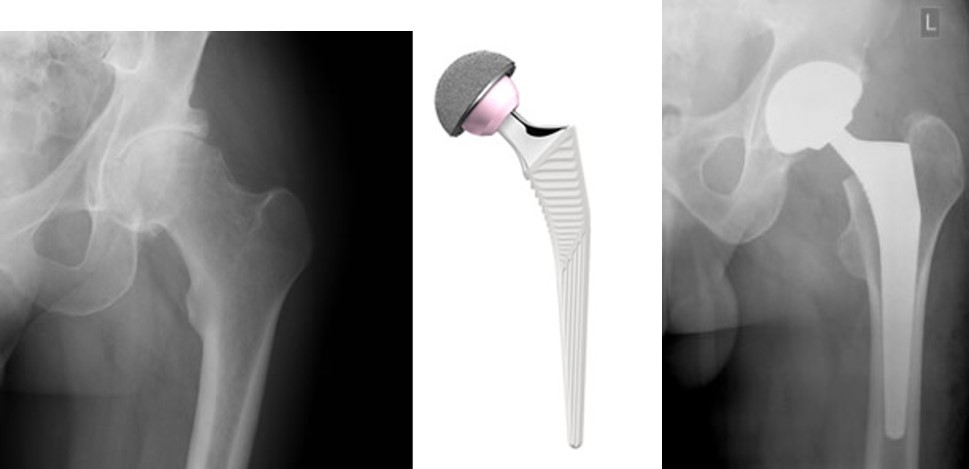

Hip X-Rays and Prosthetic Hip Joint

X-rays showing before and after hip replacement surgery, with the type of prosthetic (artificial) hip joint used in the middle.

Image: © Thackray Medical Museum